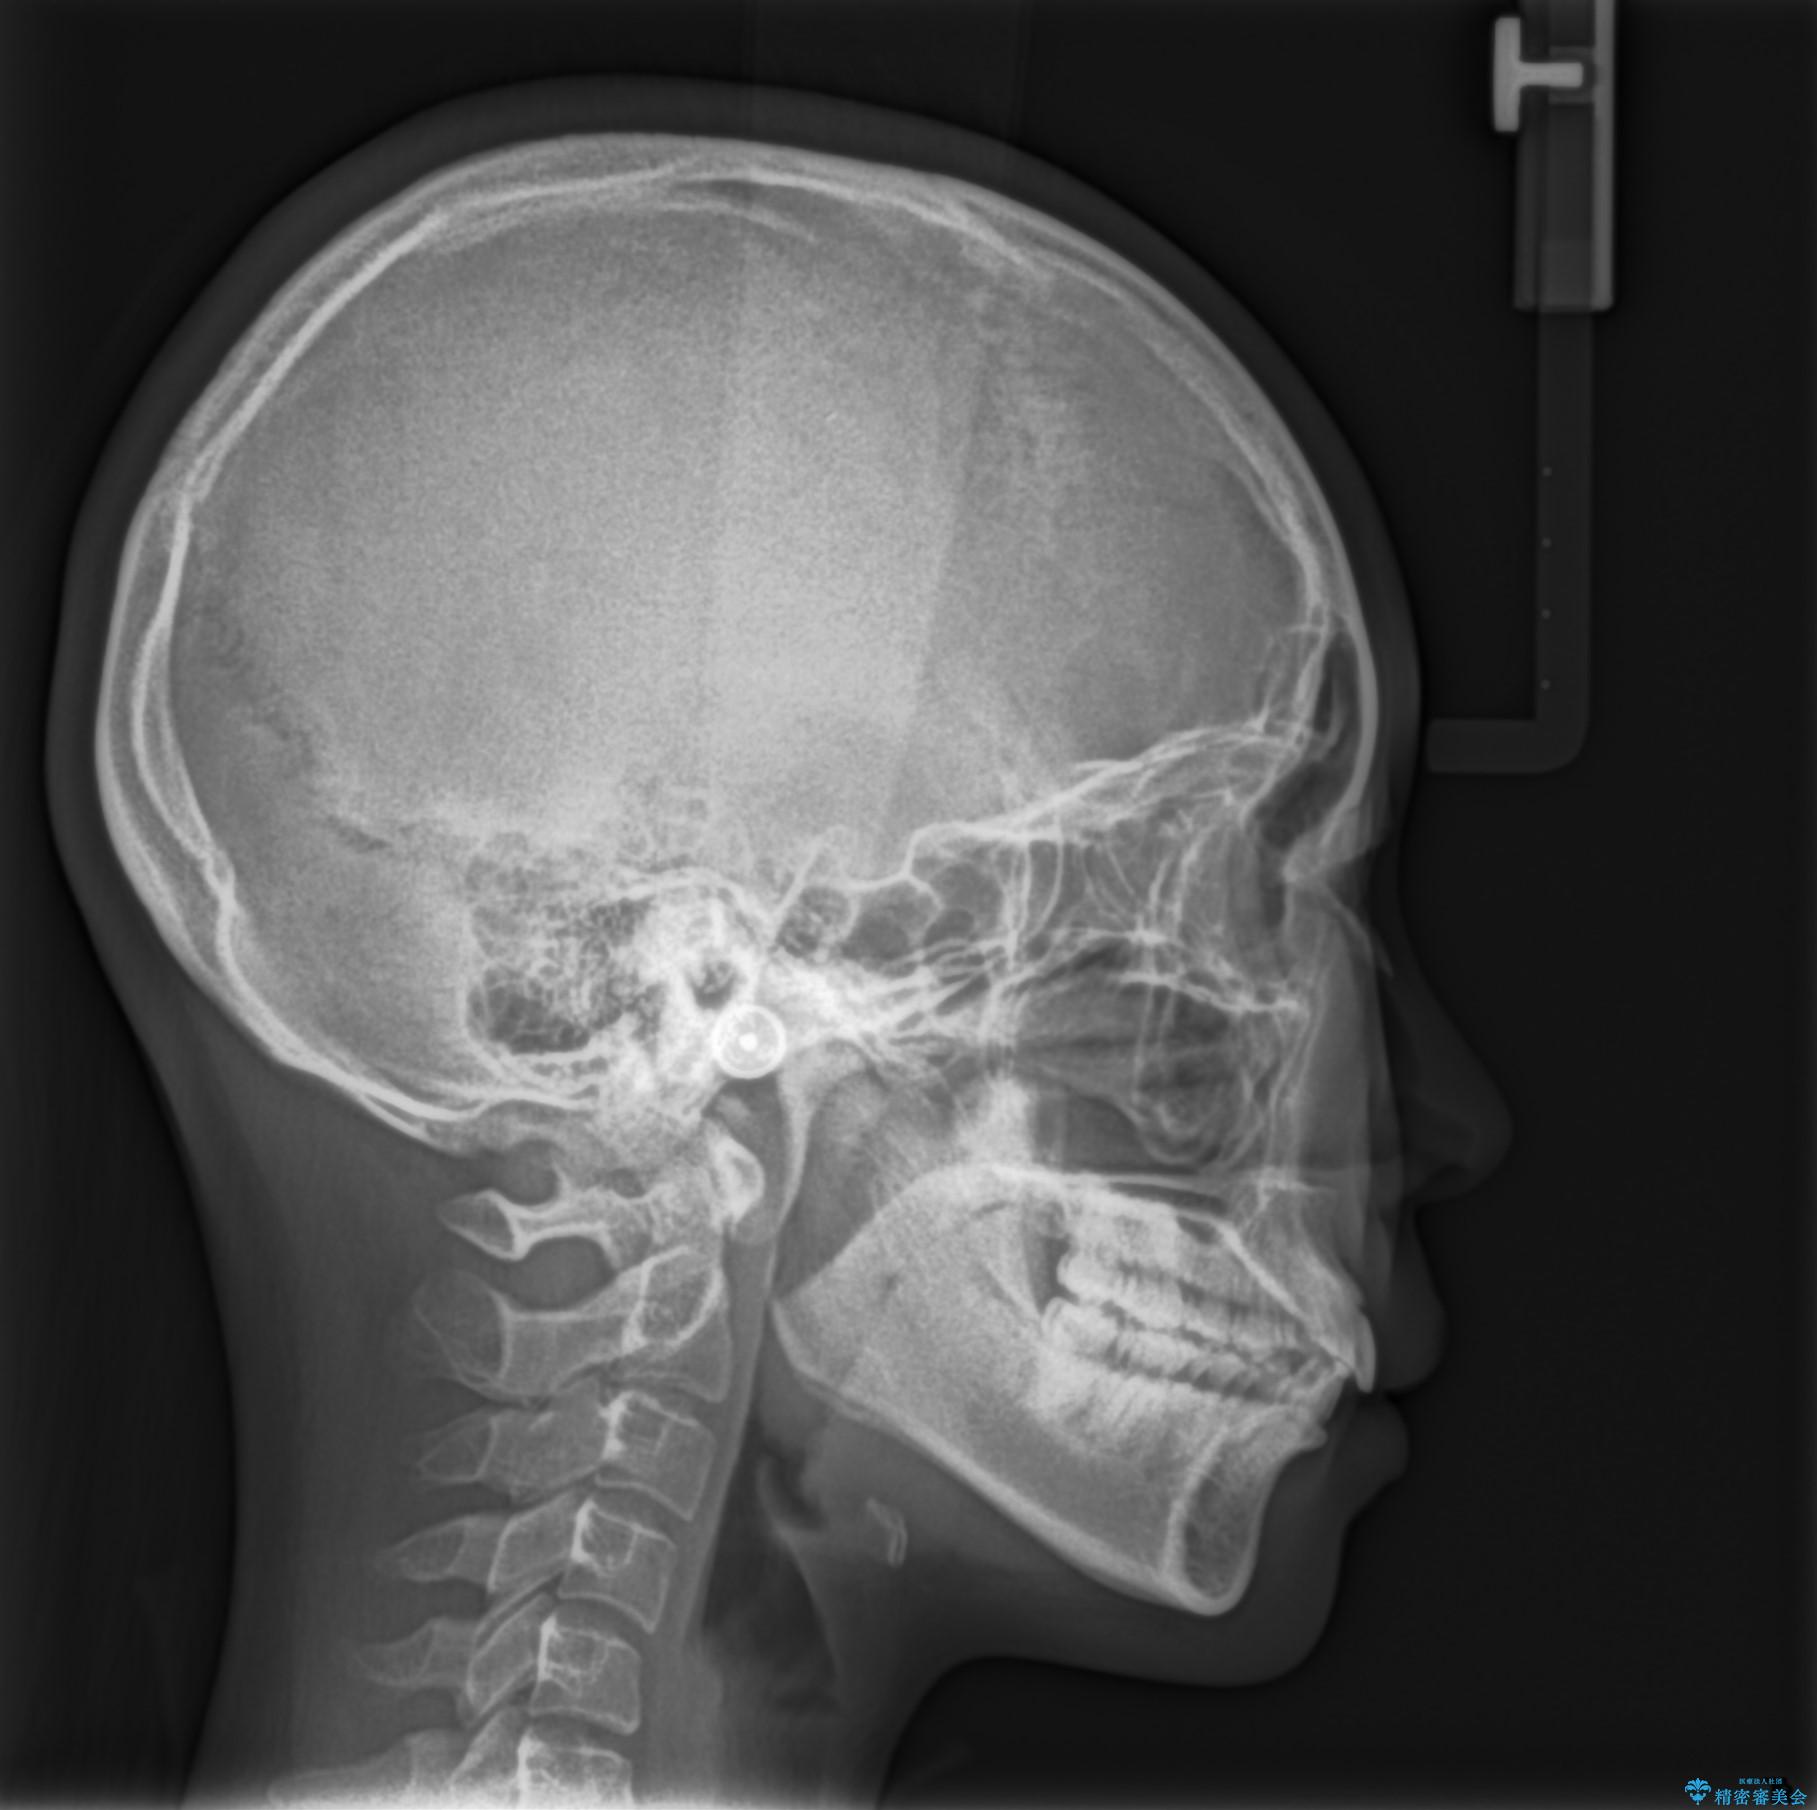

- 前歯の隙間を閉じたいと矯正カウンセリングに来られた患者様です。

マウスピース矯正(インビザライン)を行い短期間で治療が完了しました。